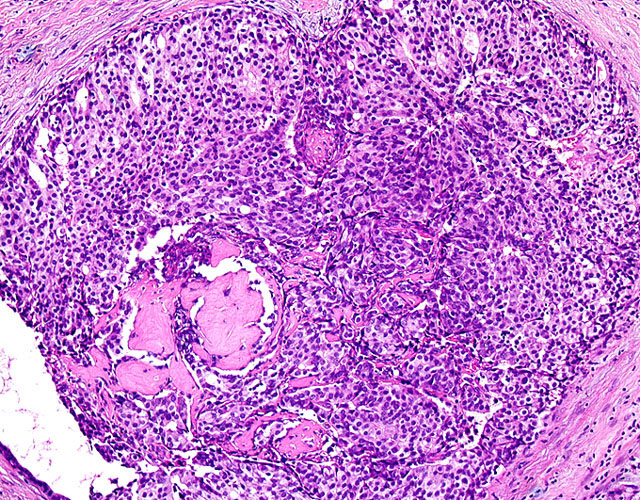

•a•Ο•”Šg‘ε‘œiHEυFj